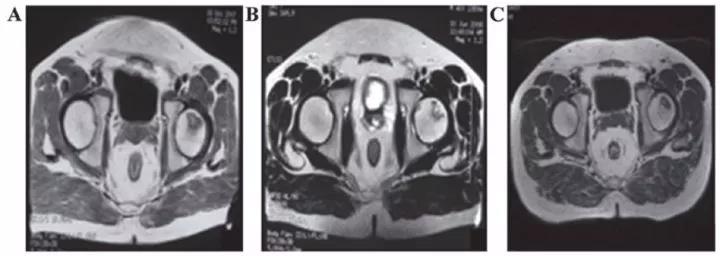

? 勃起功能障礙

運用干細胞治療勃起功能障礙一方面可以完全取代受損和死亡的陰莖組織細胞,另一方面可以分泌一些因子修復(fù)功能受損的陰莖組織細胞。

丹麥15位勃起功能障礙患者在未接受藥物或陰莖移植術(shù)的情況下接受間充質(zhì)干細胞的輸注,6個月后,8名男性能夠正常性交。